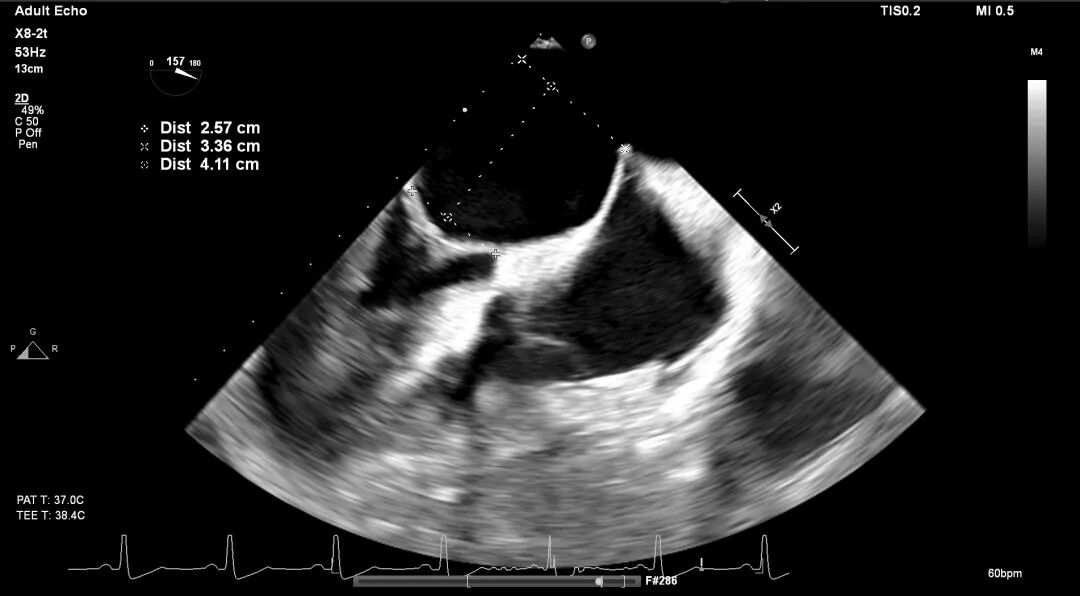

术前TEE评估

原发性MR,交界C1区脱垂,反流程度4+;二尖瓣瓣口面积3.88cm²,平均跨瓣压差2mmHg;二尖瓣前叶(A1)长度16.2mm,二尖瓣后叶长度(P1)长度9.9mm,脱垂高度6mm。